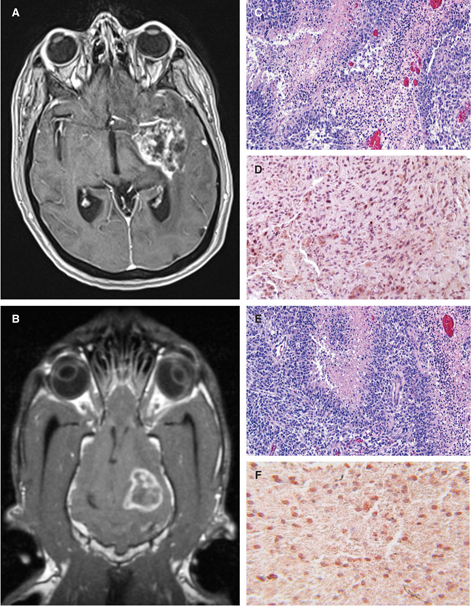

We have evaluated the safety and preliminary efficacy both IRE (Figure 3) and H-FIRE (Figure 4) in dogs with spontaneous brain tumors (77, 79, 86). An integral component of the preclinical evaluation of IRE and H-FIRE was the development of anatomically accurate numerical treatment planning models that maximize tumor coverage while minimizing damage to surrounding healthy tissue and also account for the increase in tissue conductivity that occurs during pulse delivery (8688). Incorporating therapeutic plans developed from patient-specific, segmented medical images imported into finite element analysis modeling software, we have confirmed the ability of IRE and H-FIRE to safely and precisely ablate normal and neoplastic canine brain tissues with a submillimeter line of demarcation between ablated and non-treated tissues (79, 86, 89). IRE treatment of canine gliomas resulted in significant objective tumor responses in 4/5 dogs with quantifiable target lesions (Figure 3), and these radiographic responses were accompanied by improvements in Karnofsky performance scores and posttreatment seizure control (72, 86). Similarly, using a treat and resect treatment paradigm, we have confirmed the ability of H-FIRE to safely and precisely ablate clinically relevant volumes of canine brain tumors without the induction of muscular contractions during pulse delivery (Figure 4).

Fig 3

Figure 3 Stereotactic glioblastoma ablation with irreversible electroporation (IRE). Pretreatment transverse (A) and dorsal planar (B) post-contrast T1-weighted MR demonstrating ring-enhancing glioblastoma in the frontoparietal lobe of the cerebrum. Co-registered intraoperative CT and pre-treatment MR images (C) and three-dimensional reconstructed CT (F) with IRE electrodes in situ within the tumor in preparation for ablation. Three-month post-IRE treatment transverse (D) and dorsal planar (E) post-contrast T1-weighted MR illustrating 95% reduction in tumor burden.